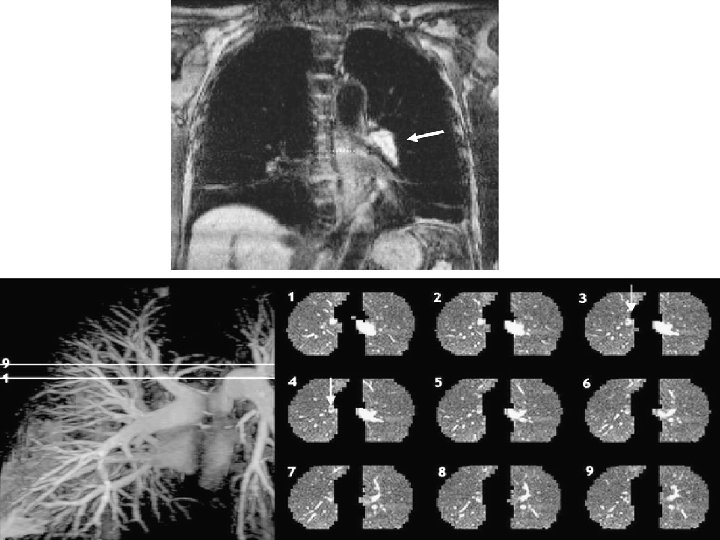

TC HELICOIDAL

Helical CT of the pulmonary arteries with intraluminal filling defects in the lobar artery of the left lower lobe (solid arrow) and the main artery of the right lung (open arrow) in a patient with a chest deformity. Kearon C CMAJ 2003; 168: 183 -194 © 2003 by Canadian Medical Association

Kearon C CMAJ 2003; 168: 183 -194 © 2003 by Canadian Medical Association